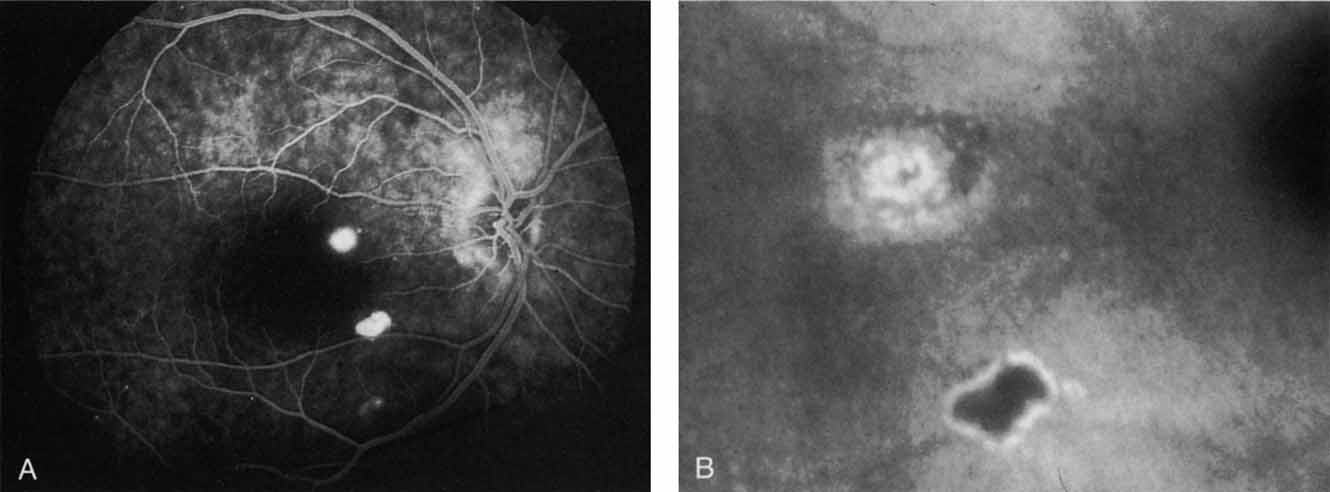

OCULAR HISTOPLASMOSIS SYNDROME

In contrast to multifocal choroiditis, ocular histoplasmosis syndrome does not demonstrate any large, hypofluorescent lesions on the ICG angiographic examination.69 Instead, there are frequently mid- and late-phase hyperfluorescent lesions in the posterior pole in areas that appear normal both clinically and on fluorescein angiography (Fig. 19). These hyperfluorescent lesions may represent sites of subclinical choroidal inflammation. The presence of these lesions on ICG angiography not only may serve to distinguish the histoplasmosis syndrome but also may serve to explain the apparent de novo appearance of new atrophic spots and CNV in what was previously presumed to be normal chorioretinal tissue.

Fig. 19 A. Clinical photograph of a patient with recurrent choroidal neovascularization associated with ocular histoplasmosis syndrome. A few focal “histo spots” are noted in the superior macula. B. Late-phase indocyanine green study demonstrating hyperfluorescence in the central macula corresponding to recurrent neovascularization. Multiple intensely hyperfluorescent dots are noted throughout the macular region, which do not correspond to any detectable lesion noted clinically or via fluorescein angiography. These focal spots may represent sites of subclinical inflammation at the level of the choroid.